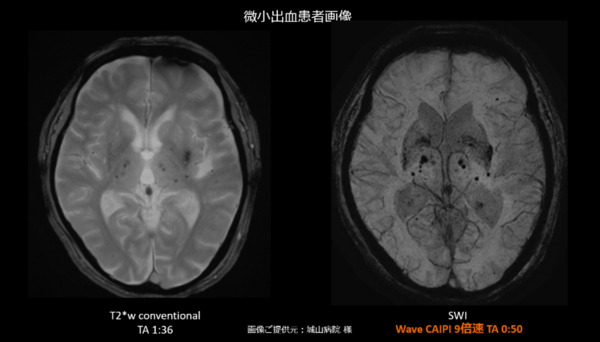

●撮像時間を大幅に短縮しながら高分解能な磁化率強調画像を取得するWave-CAIPI SWI技術

従来,SWI(Susceptibility Weighted Imaging:磁化率強調画像)は,微小出血や静脈構造を高感度に描出できる一方,高分解能の3D撮像が必要なため撮像時間が長く,ルーチン検査に組み込みにくいという課題があった。Wave-CAIPI技術を⽤いたSWIでは,撮像時間を大幅に短縮しながら高分解能なSWIを取得することが可能である。これにより,多発性硬化症において重要視される中心静脈サイン(Central Vein Sign:病変中心を走行する静脈所見)などの描出を,ルーチン検査の延長を抑えながら,診断精度向上に貢献する。